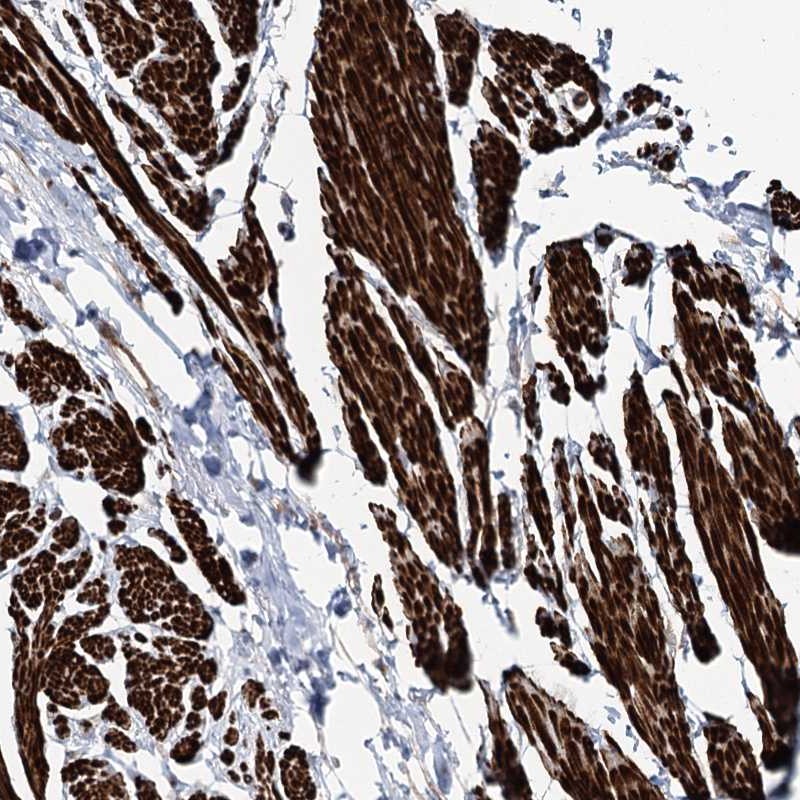

Immunohistochemical staining of human smooth muscle shows strong cytoplasmic positivity in smooth muscle cells.